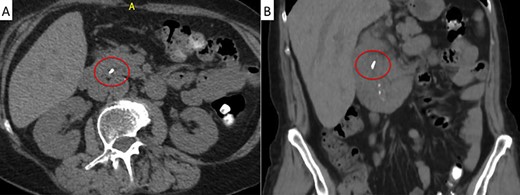

A 71-year-old woman with a history of LC for acute cholecystitis 6 years earlier was admitted with right upper quadrant abdominal pain, jaundice and fever. On admission, her vital signs were body temperature 38.2°C, pulse rate 96/min, respiration rate 21/min, blood pressure 100/60 mmHg and SpO2 98%. Her laboratory tests showed leukocytosis (19.200/ml), an erythrocyte sedimentation rate of 25 mm/h, C-reactive protein of 26 mg/l and altered liver function tests with cholestatic pattern: total bilirubin 4.95 mg/dl (normal up to 1.2), direct bilirubin 4.18 mg/dl, alkaline phosphatase 1083 IU/l (normal up to 150), gamma-glutamyl transferase 169 IU/l (normal up to 45), aspartate transaminase 281 IU/l (normal up to 40) and alanine transaminase 330 IU/l (normal up to 41). Serum amylase and lipase were normal. Abdominal ultrasound showed biliary tract dilatation but not obstructive cause, with a maximum diameter of the CBD of 17.6 mm. A subsequent magnetic resonance cholangiopancreatography (MRCP) found a filling defect in the distal CBD (Fig. 1). ERCP extraction was attempted, but it was impossible to progress the catheter due to an irregular distal bile duct stenosis. An abdominal computed tomography (CT) scan was therefore performed and showed a foreign body with radiopaque characteristics in the distal CBD consistent with a metallic clip (Fig. 2). Given that the object could not be removed by ERCP due to technical difficulties in biliary cannulation, laparoscopic bile duct exploration was decided.

Abdominal CT scan. A metallic artifact is observed in the distal common bile duct (red circle) in axial (A) and coronal (B) planes.